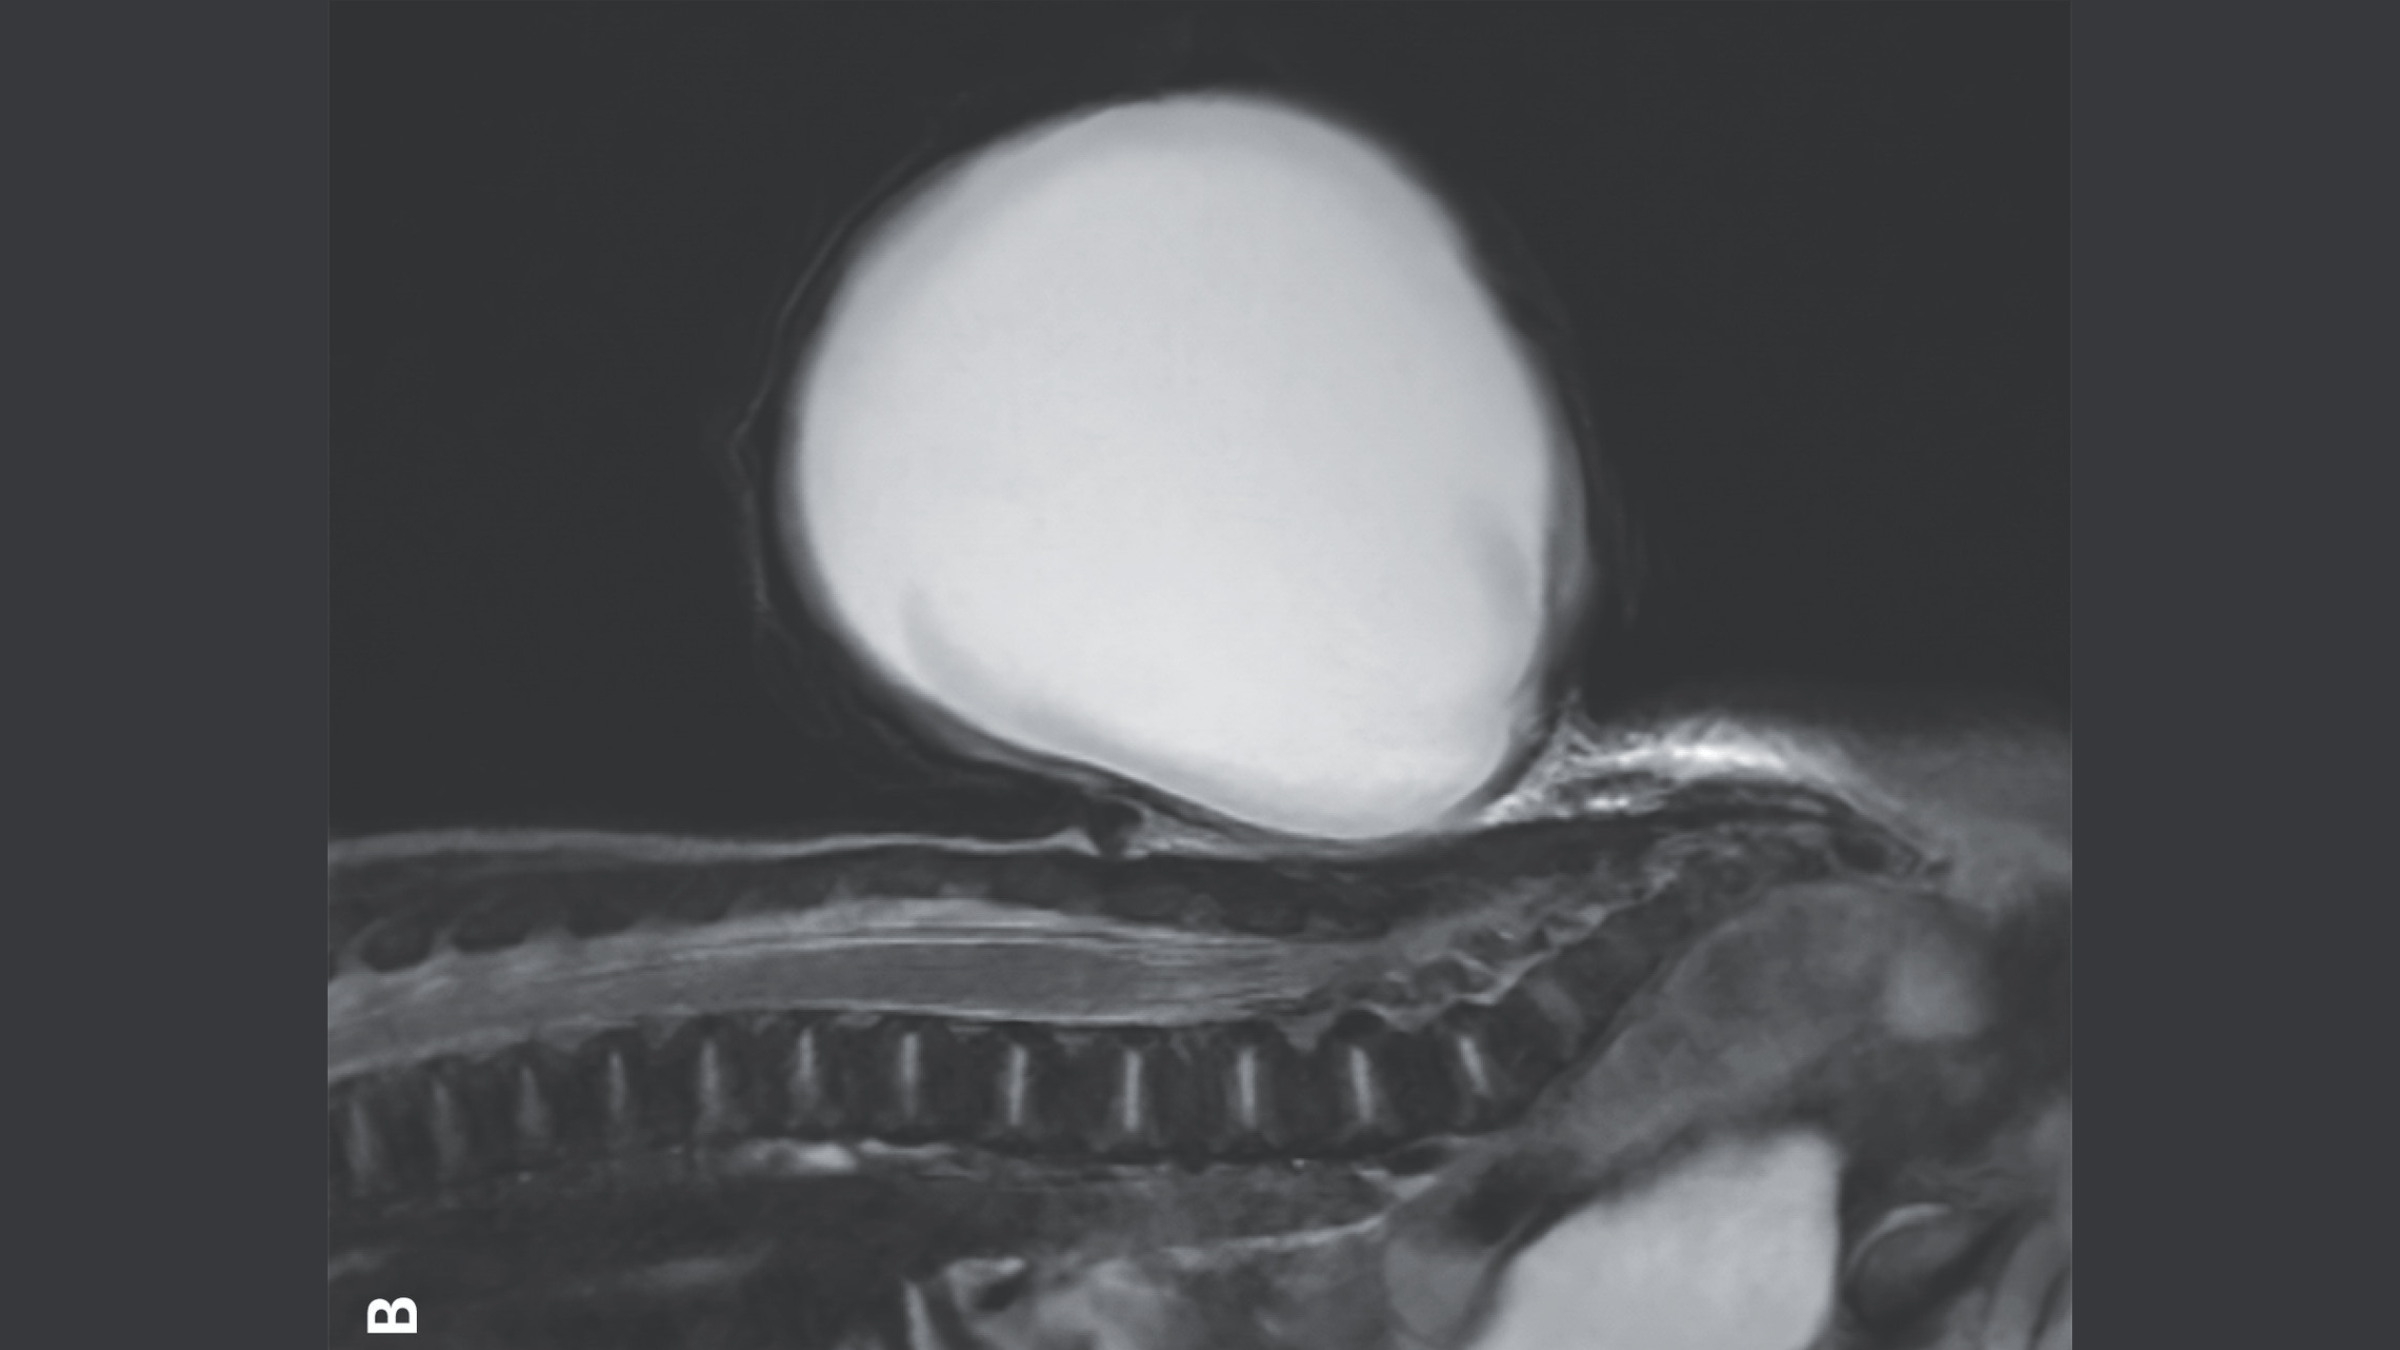

The balloon-like sac of tissue and fluid that grew from the baby’s spine shown on a magnetic resonance imaging (MRI) scan.

now and again , though , tissue and fluid that embrace and protects the spinal cord is crowd through the interruption , create a sac - like , protruding body structure . This is what happened to the boy in the image , who had a specific version of spina bifida called meningocele .

doctor first noticed the spinal shortcoming during an sonography exam around 20 weeks , orhalfway through , the maternity . affected role with meningocele often have small problems such asissues with their vesica and bowels . However , the condition can usually be treat witha simple surgical repair , eitherbeforeorafter birth .

The sac-like protrusion (pictured above) was caused by a condition known as meningocele.(Image credit: The New England Journal of Medicine ©2024)